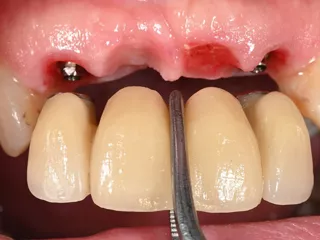

Dr Nuño GIL, Spain In this case, we encountered the challenge of unequal hard and soft tissue volumes and heights in already healed areas versus post-extraction sockets. Read more